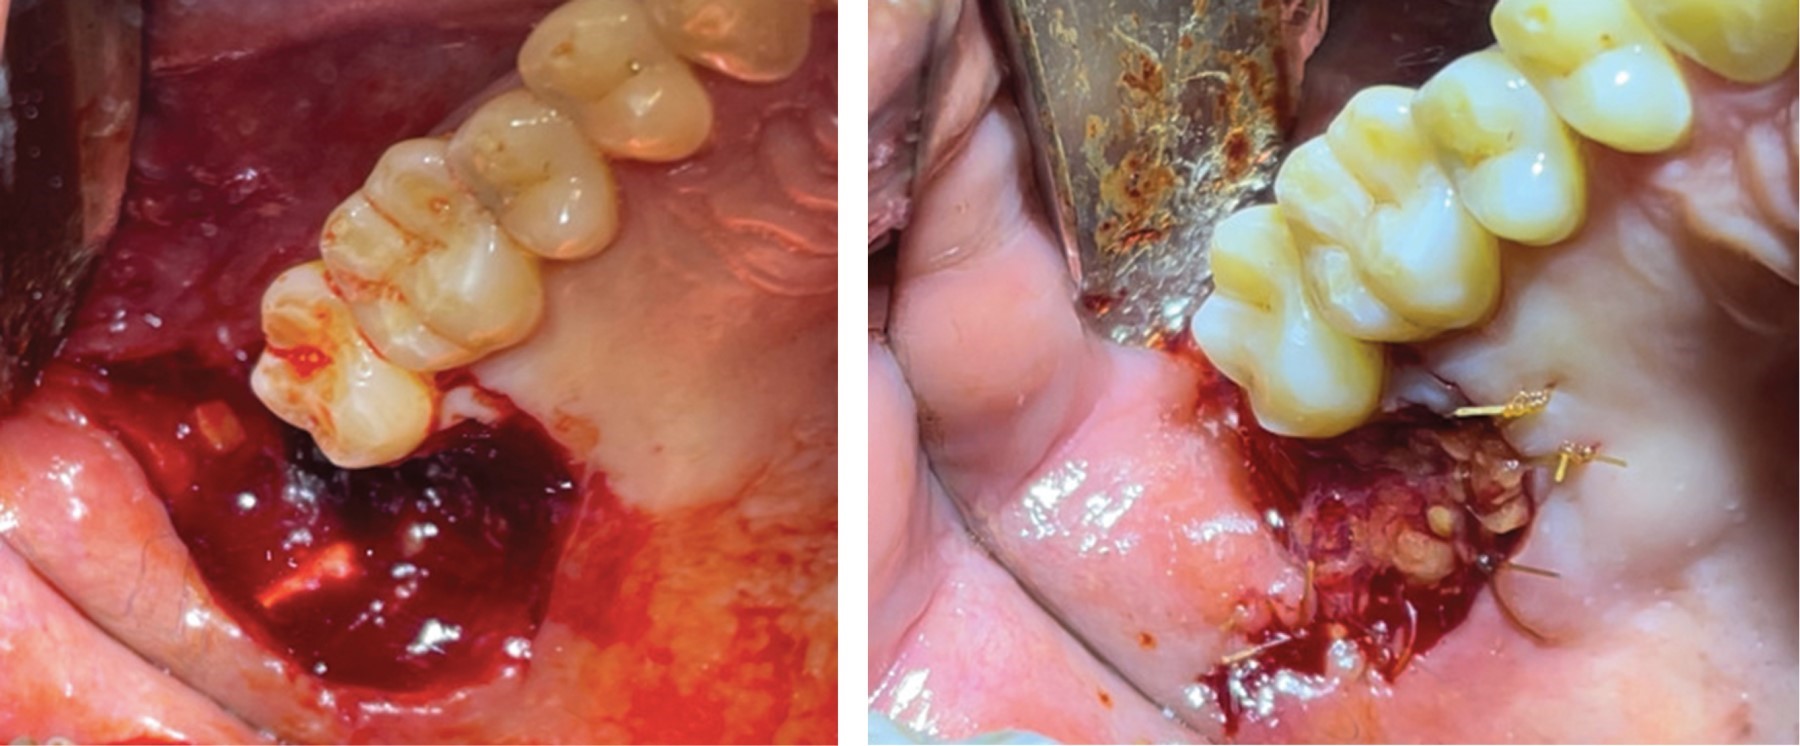

El paciente inicia su padecimiento alrededor de noviembre y diciembre de 2022, notando un aumento de volumen en la zona del molar 28. De manera posterior, en diciembre de 2022, el paciente refiere inflamación, sangrado espontáneo y dolor moderado, por lo que acudió al servicio odontológico externo y se le prescribió clindamicina de 300 mg vía oral, cada 8 horas y ketoprofeno de 100 mg vía oral, cada 8 horas, con mejoría parcial del dolor, persistiendo el sangrado espontáneo, por lo que acude a consulta privada. Paciente con signos vitales estables, a la exploración de cavidad oral se identifica una úlcera de bordes indurados en maxilar adyacente a la zona del molar 28, de un aproximado de 2 × 2 cm, de consistencia firme y asintomático a la palpación (Figura 1).

Se realiza biopsia escisional y exodoncia del molar 28, en la misma intervención, en enero de 2022 (Figuras 3 y 4). No se suspende medicación de clindamicina hasta finalizar el esquema y se prescriben analgésicos y una dosis única de betametasona inyectable, vía intramuscular 8.0 mg/2 mL.